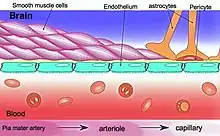

Blood–brain barrier dysfunction

The blood–brain barrier (BBB) is essential in maintaining a homeostatic environment for neurons and glial cells by preventing solutes from diffusing into the brain interstitial space. The endothelial cells that makeup the BBB are different from those that make up the vasculature structurally, molecularly, and metabolically. They are connected by tight junctions, which further ensure that molecules do not freely pass through.

BBB disruption is associated with hypertension, cerebrovascular diseases, neurodegenerative diseases, and aging.

The endothelium plays a critical role in regulating blood vessels throughout the body, modulating the function of cells with the vessel walls and even non-vascular cells. For example, the endothelium releases cytokines and expresses adhesion molecules that recruit leukocytes, which is important in inflammation.[10] The endothelium influences vascular muscle by regulating vascular tone and it also determines vascular permeability into the tissues— tight junctions between endothelial cells are pertinent in the blood brain barrier.[11]